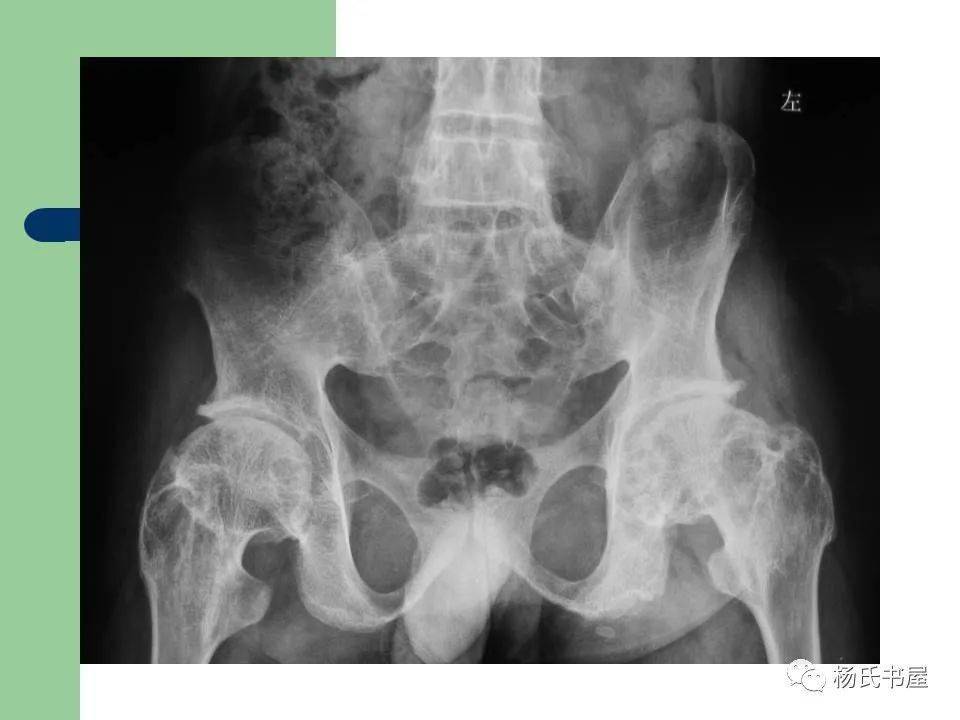

类风湿患者为何会骨质疏松?许多类风湿病患者在来医院接受治疗时被诊断出患有骨质疏松症,这使得治疗更加复杂。他们想知道,他们并不老,如何得骨质疏松症? 类风湿和骨质疏松如影随形 多年的临床实践和科学研究证实,类风湿病患者骨质疏松甚至脆性骨折的发病率明显高于正常群体。 由于类风湿继发性骨质疏...